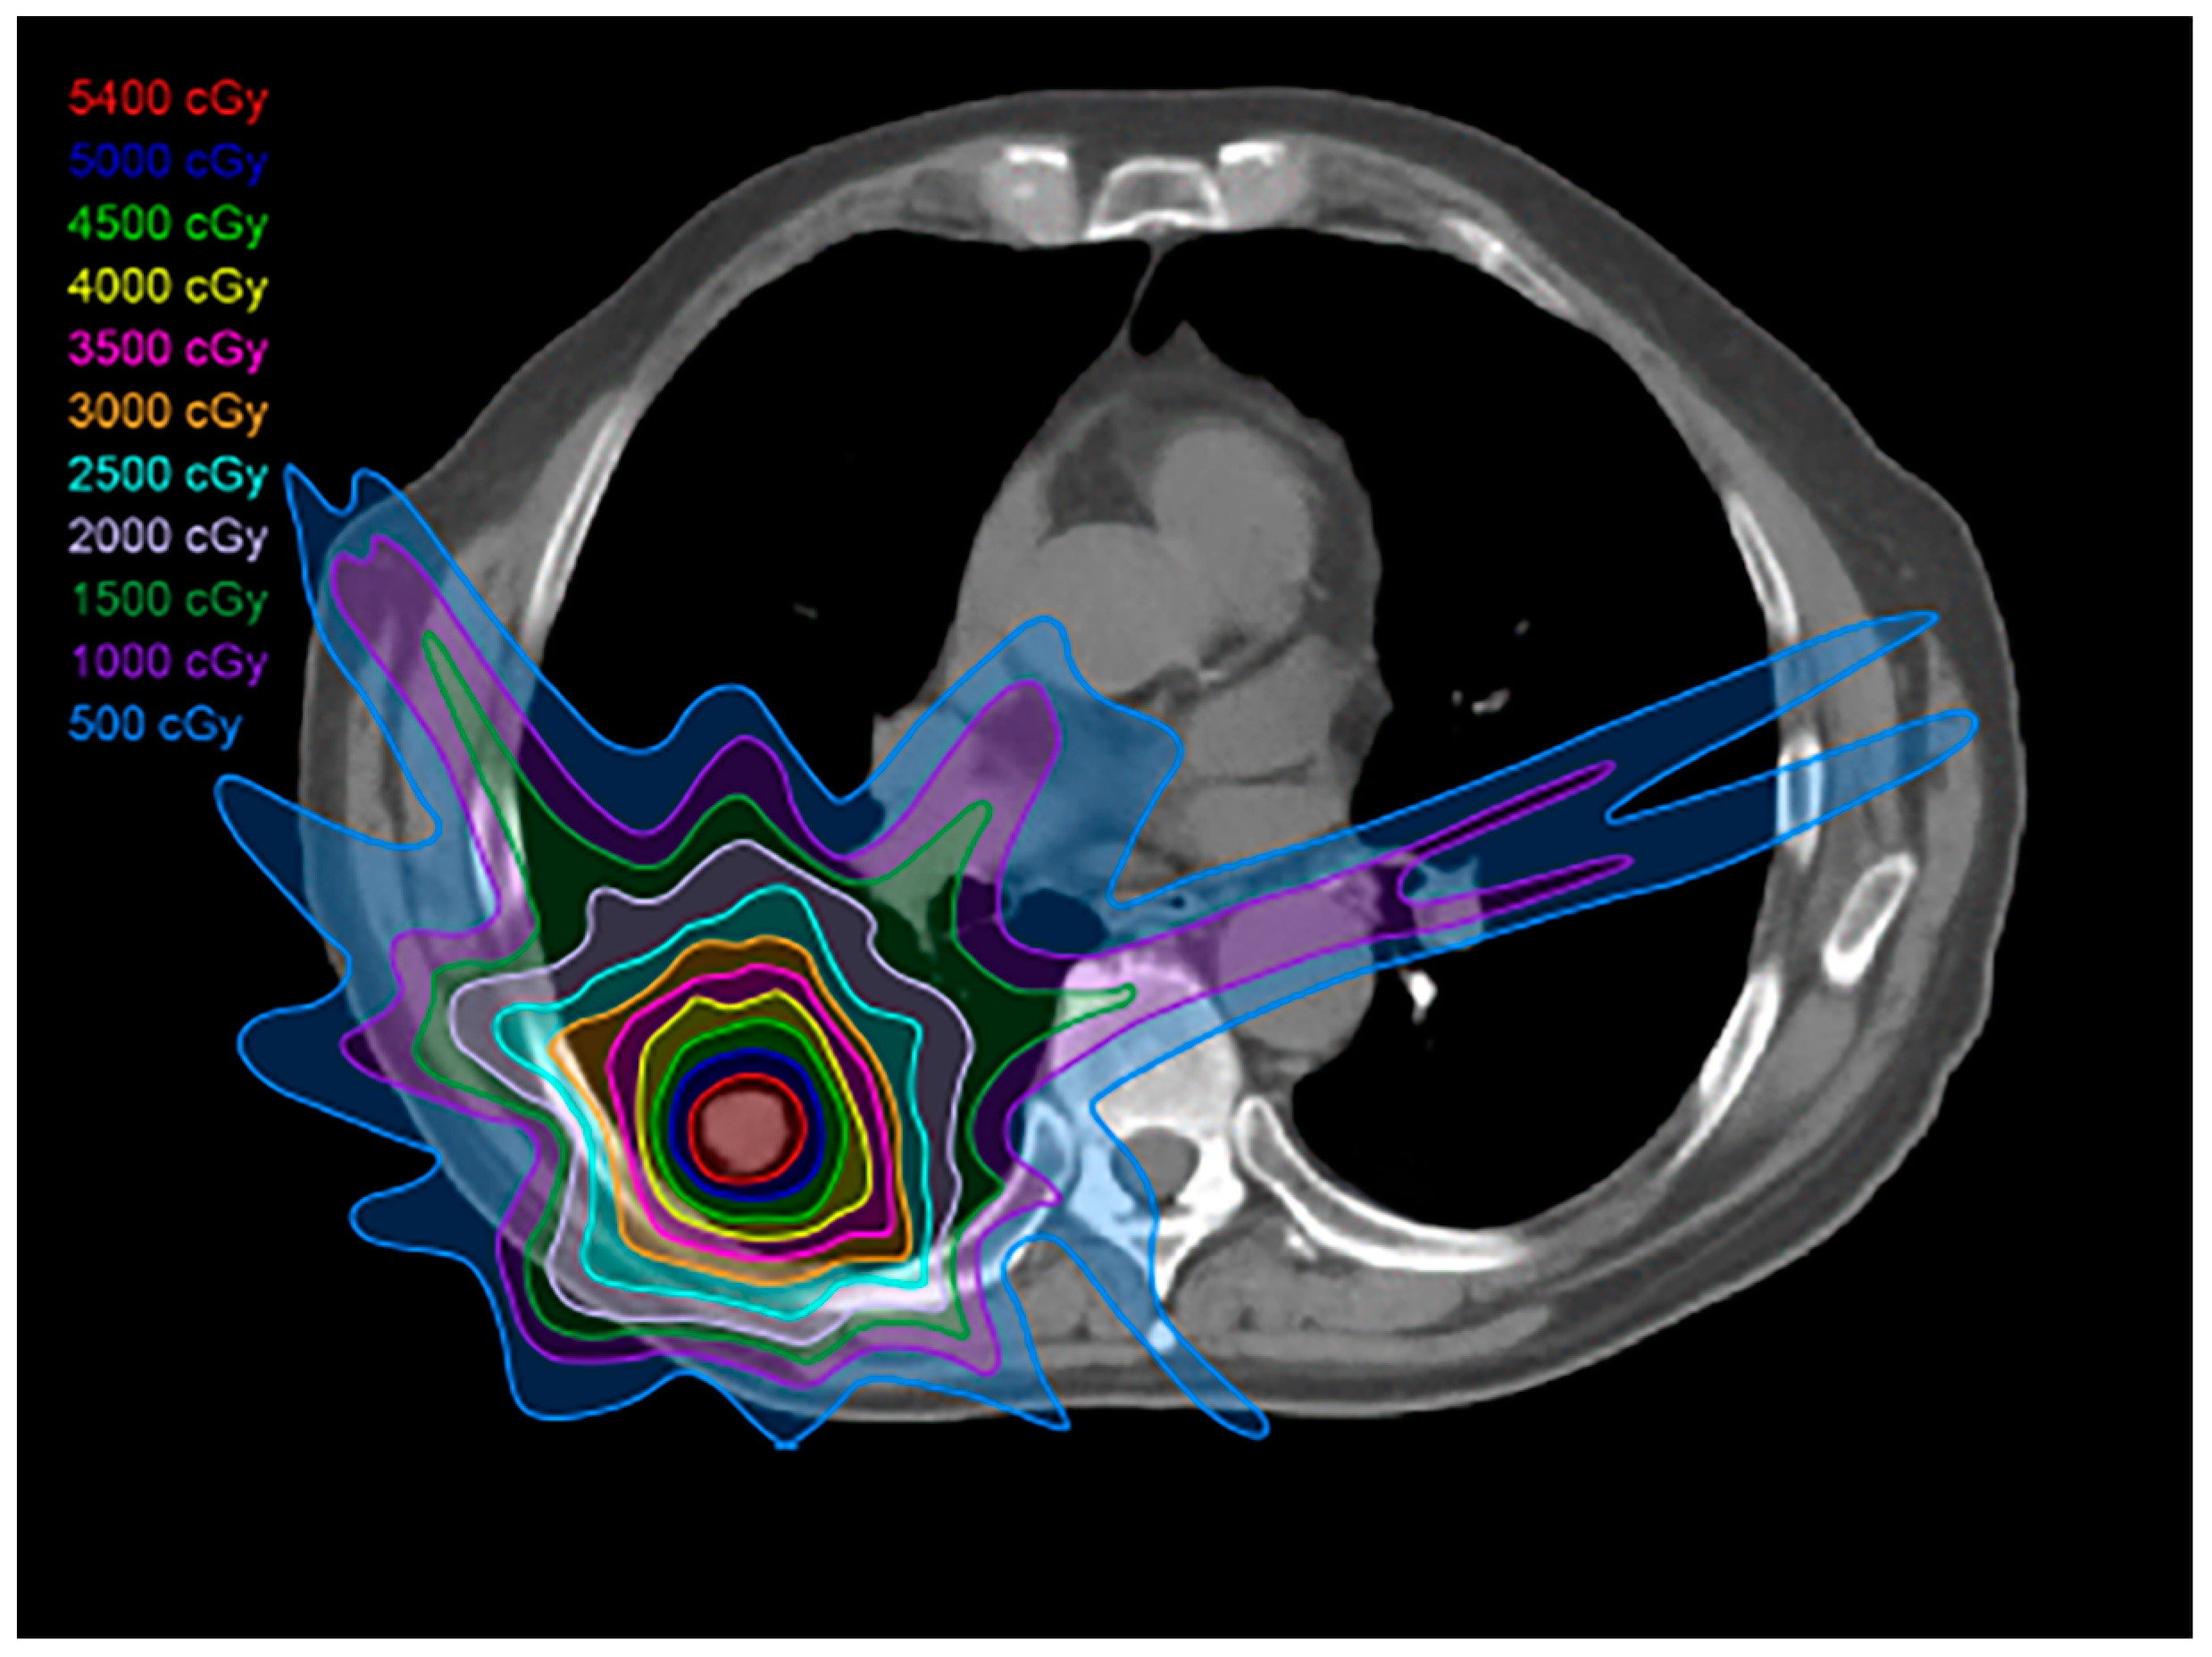

2.2. Three-Dimensional Conformal Radiotherapy

2.3. Intensity-Modulated Radiotherapy

2.4. Stereotactic Body Radiotherapy

2.5. Four-Dimensional Conformal Radiotherapy

2.6. Proton Therapy